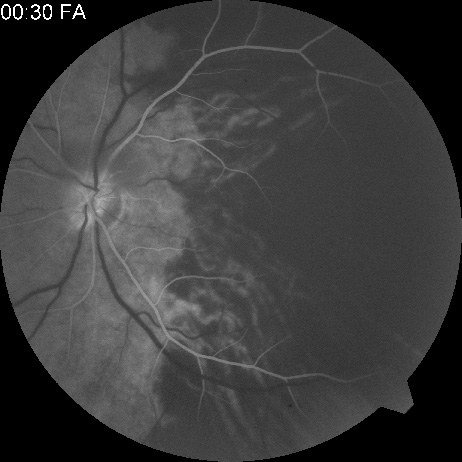

OBSTRUCTION OF THE OPHTHALMIC ARTERY, POSTERIOR CILIARY ARTERIES, OR ARTERIES SUPPLYING THE CHORIOCAPILLARIS Symptoms that involve obstruction of the ophthalmic artery, posterior ciliary arteries, or arteries supplying the choriocapillaris depend on which artery is affected. In some patients, the location of the obstruction must be inferred because it is not always possible to visualize it, even with intravenous fluorescein angiography. The ophthalmic artery is a branch of the carotid artery that branches into the central retinal artery and the posterior ciliary arteries.115 There are usually two main ciliary arteries; each one supplies about half of the choroid. The medial posterior ciliary artery supplies the nasal half, and the lateral posterior ciliary artery supplies the temporal half, with a watershed zone in between. The branches of the medial and lateral posterior ciliary arteries (and occasionally a superior ciliary artery) become the long or short posterior ciliary artery.116,117 Each lobule of the choriocapillaris supplied by the terminal choroidal arteriole forms one of the branches of the posterior ciliary artery, and each lobule is drained by a venule.116,118There is no anastomotic communication between lobules. OPHTHALMIC ARTERY OBSTRUCTION Ophthalmic artery obstruction is characterized by an initial opacification of the entire retina in a manner similar to that of central retinal artery obstruction (Fig. 4A). The cherry-red spot may or may not be present, however.119 The difference between an ophthalmic artery obstruction and central retinal artery obstruction is that in an ophthalmic artery obstruction, with time, optic atrophy develops, as does varying amounts of pigmentation due to the lack of perfusion of the retinal pigment epithelium (see Fig. 4D). This pigment is generally diffusely scattered throughout the posterior pole but it may also be seen in greater amounts in the periphery.

Intravenous fluorescein angiography generally shows moderate to marked abnormalities in the filling of the choroid, in addition to a delay in filling or even nonfilling of retinal vessels (see Fig. 4B and 4C). Staining of the retinal pigment epithelium can also be seen; this staining either can occur locally in the macular area or it can be diffuse.119 The electroretinogram shows abnormalities of both a- and b-waves, reflecting ischemia to both the inner and outer retina. Almost all reported patients have had an initial visual acuity of no light perception; virtually no patients can be expected to have a final visual acuity better than that.119 An acuity of no light perception is a clue to the presence of an ophthalmic artery obstruction. Because relatively few patients with central retinal artery obstruction have an initial visual acuity of no light perception, no light perception usually suggests the likelihood of some obstruction of the choroidal circulation.14 The causes of ophthalmic artery obstruction vary. In the 10 eyes reported by Brown and co-workers,119 the cause in 2 patients was carotid artery disease. In 1 patient each, the following causes were found: embolization from an arterial myxoma, atrial fibrillation, external compression of the orbit and globe, trauma (a knife wound), orbital mucormycosis, and one of unknown cause.119 Because the ophthalmic artery makes an acute bend in the orbit, it is likely that emboli could lodge at that location.115,120 The site of this type of obstruction must be speculative, however, because there is no way to know that a simultaneous obstruction of the retinal and the choroidal circulation has not occurred distal to the ophthalmic artery. Two of the cases reported by Brown and coworkers119 were bilateral. One occurred in a patient with bilateral mucormycosis and the other was in a patient experiencing atrial fibrillation with accompanying thyroid fever.119 Patients with a presumed ophthalmic artery obstruction require careful and complete systemic evaluation in the search for possible causes. POSTERIOR CILIARY ARTERY OBSTRUCTION Obstruction of one of the posterior ciliary arteries may result in a whitening of the area of the retina supplied by the involved posterior ciliary artery and the subsequent appearance of patchy pigmentation in the same area. However, in patients with anterior ischemic optic neuropathy secondary to temporal arteritis the retina may appear normal (Fig. 5). In the case of either the medial posterior ciliary artery or the lateral posterior ciliary artery, the area involved is the size of approximately half of the choroid.121–123 In the case of a long posterior ciliary artery, the temporal side of the eye including the macula is involved.121